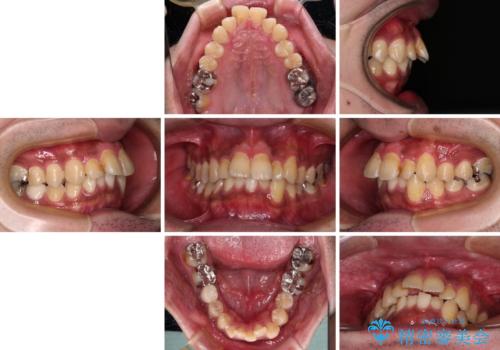

- 主張してる上の前歯を気にして来院された患者様です。

上の前歯が出ているものの、口元が出っ歯というわけではなかったため、非抜歯矯正にて治療を行うこととしました。

下顎に対して上顎歯列が全体的に前方に位置しており、特に右側の奥歯の咬み合わせの前後のズレが大きいため、補助装置を用いて咬み合わせを改善することとしました。